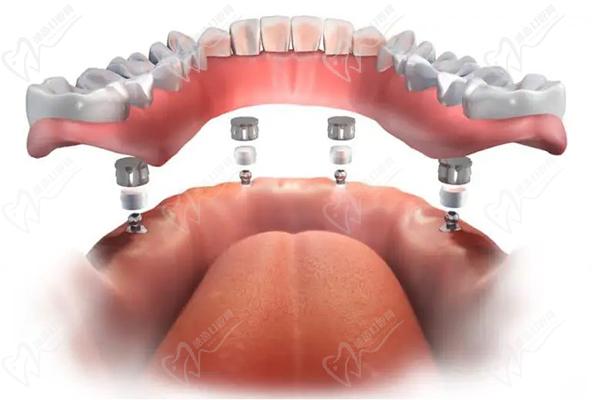

第五步:牙冠裝配

裝配過程通常被視為一個緊急過程,可以在接下來的幾小時或幾天內(nèi)完成。醫(yī)生將確定所有材料是否適合,并調(diào)整和調(diào)整新牙齒到正確的位置。